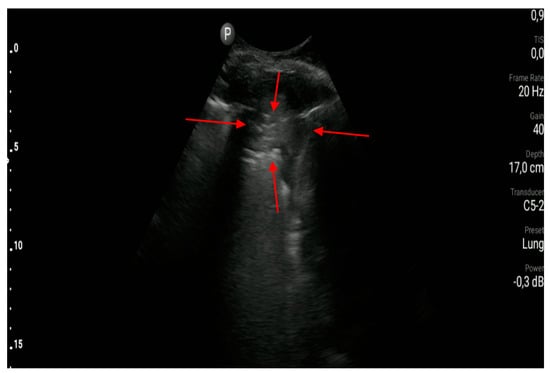

- The sonographic features of interstitial syndrome are as follows: the presence of lung sliding and ≥3 B-line artifacts in one intercostal space in a single longitudinal scan plane (in relation to the body axis). (A1)

- B-line artifacts are laser-like vertical reverberation artifacts arising from the pleural line, extending to the bottom of the screen, and moving along with the movements of the pleural line. The definition of a B-line artifact is based on the use of convex/micro-convex transducers.

- The sonographic features of cardiogenic pulmonary edema are as follows: most frequently bilateral, gravitational and symmetrical interstitial syndrome, and/or alveolar-interstitial syndrome and/or the white lung sign. (A1)

- Interstitial syndrome, alveolar-interstitial syndrome and the white lung sign define successively occurring more advanced stages of interstitial lesions in the course of cardiogenic pulmonary edema. All three of these signs require that at least three B-line artifacts be found in one intercostal space in a single longitudinal scan plane (in relation to the body axis); however, the distance between individual B-line artifacts decreases with an increasing fluid volume in the interstitial space and in the alveoli.

- The sonographic features of interstitial lung disease involving pulmonary fibrosis are as follows: the lung sliding sign, the presence of ≥3 B-line artifacts in one intercostal space (a longitudinal scan plane in relation to the body axis) and pleural line abnormalities. (A1)

- Pleural line abnormalities found in patients with pulmonary fibrosis are described as irregular, coarse in appearance, fragmented or blurred.